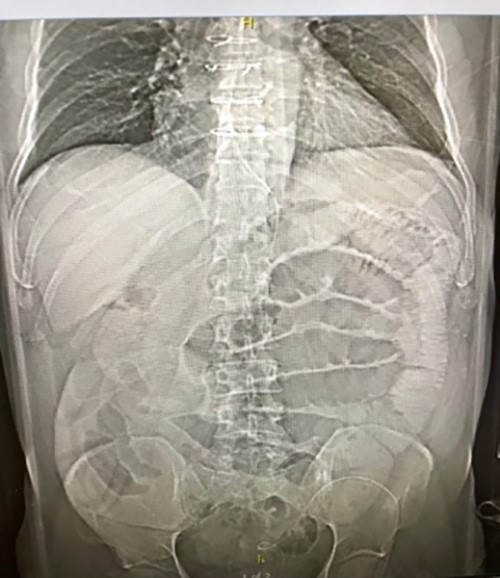

The patient underwent laparoscopic total proctocolectomy with trans-anal total mesorectal excision and end ileostomy. The patient tolerated liquid diet postoperatively. However, on postoperative day three, developed nausea, vomiting and increased abdominal distention with absent ileostomy output. Abdominal X ray (Figure 2) showed diffuse distention consistent with postoperative ileus. Decompression with nasogastric tube yielded 1.5 liter output.

Figure 2. X ray showing dilated loops of bowel.